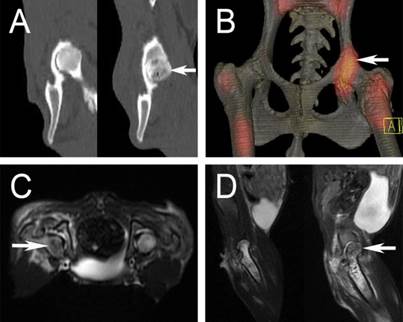

CT, radionuclide and MRI imaging

Six weeks after the operation, five animals in group 2 underwent CT and radionuclide imaging. In CT, there were several areas of low bone mineral density below the articular surface in the experimental femoral heads (Figure 7A, white arrow), which were accompanied with substantial sclerosis. Radioisotope imaging revealed an increased uptake of the nuclide species in the experimental femoral heads (figure 7B, white arrow). MRI examination showed an inhomogeneous long T2 signal in the experimental femoral heads, indicative of osteonecrosis (figure 7C and 7D, white arrow).

Figure 7

A: CT scan showed osteonecrosis in the right femoral head (white arrow); B: a “warm” change in radioisotope image (white arrow); C and D: inhomogeneous long T2 change in MRI examination (white arrow).